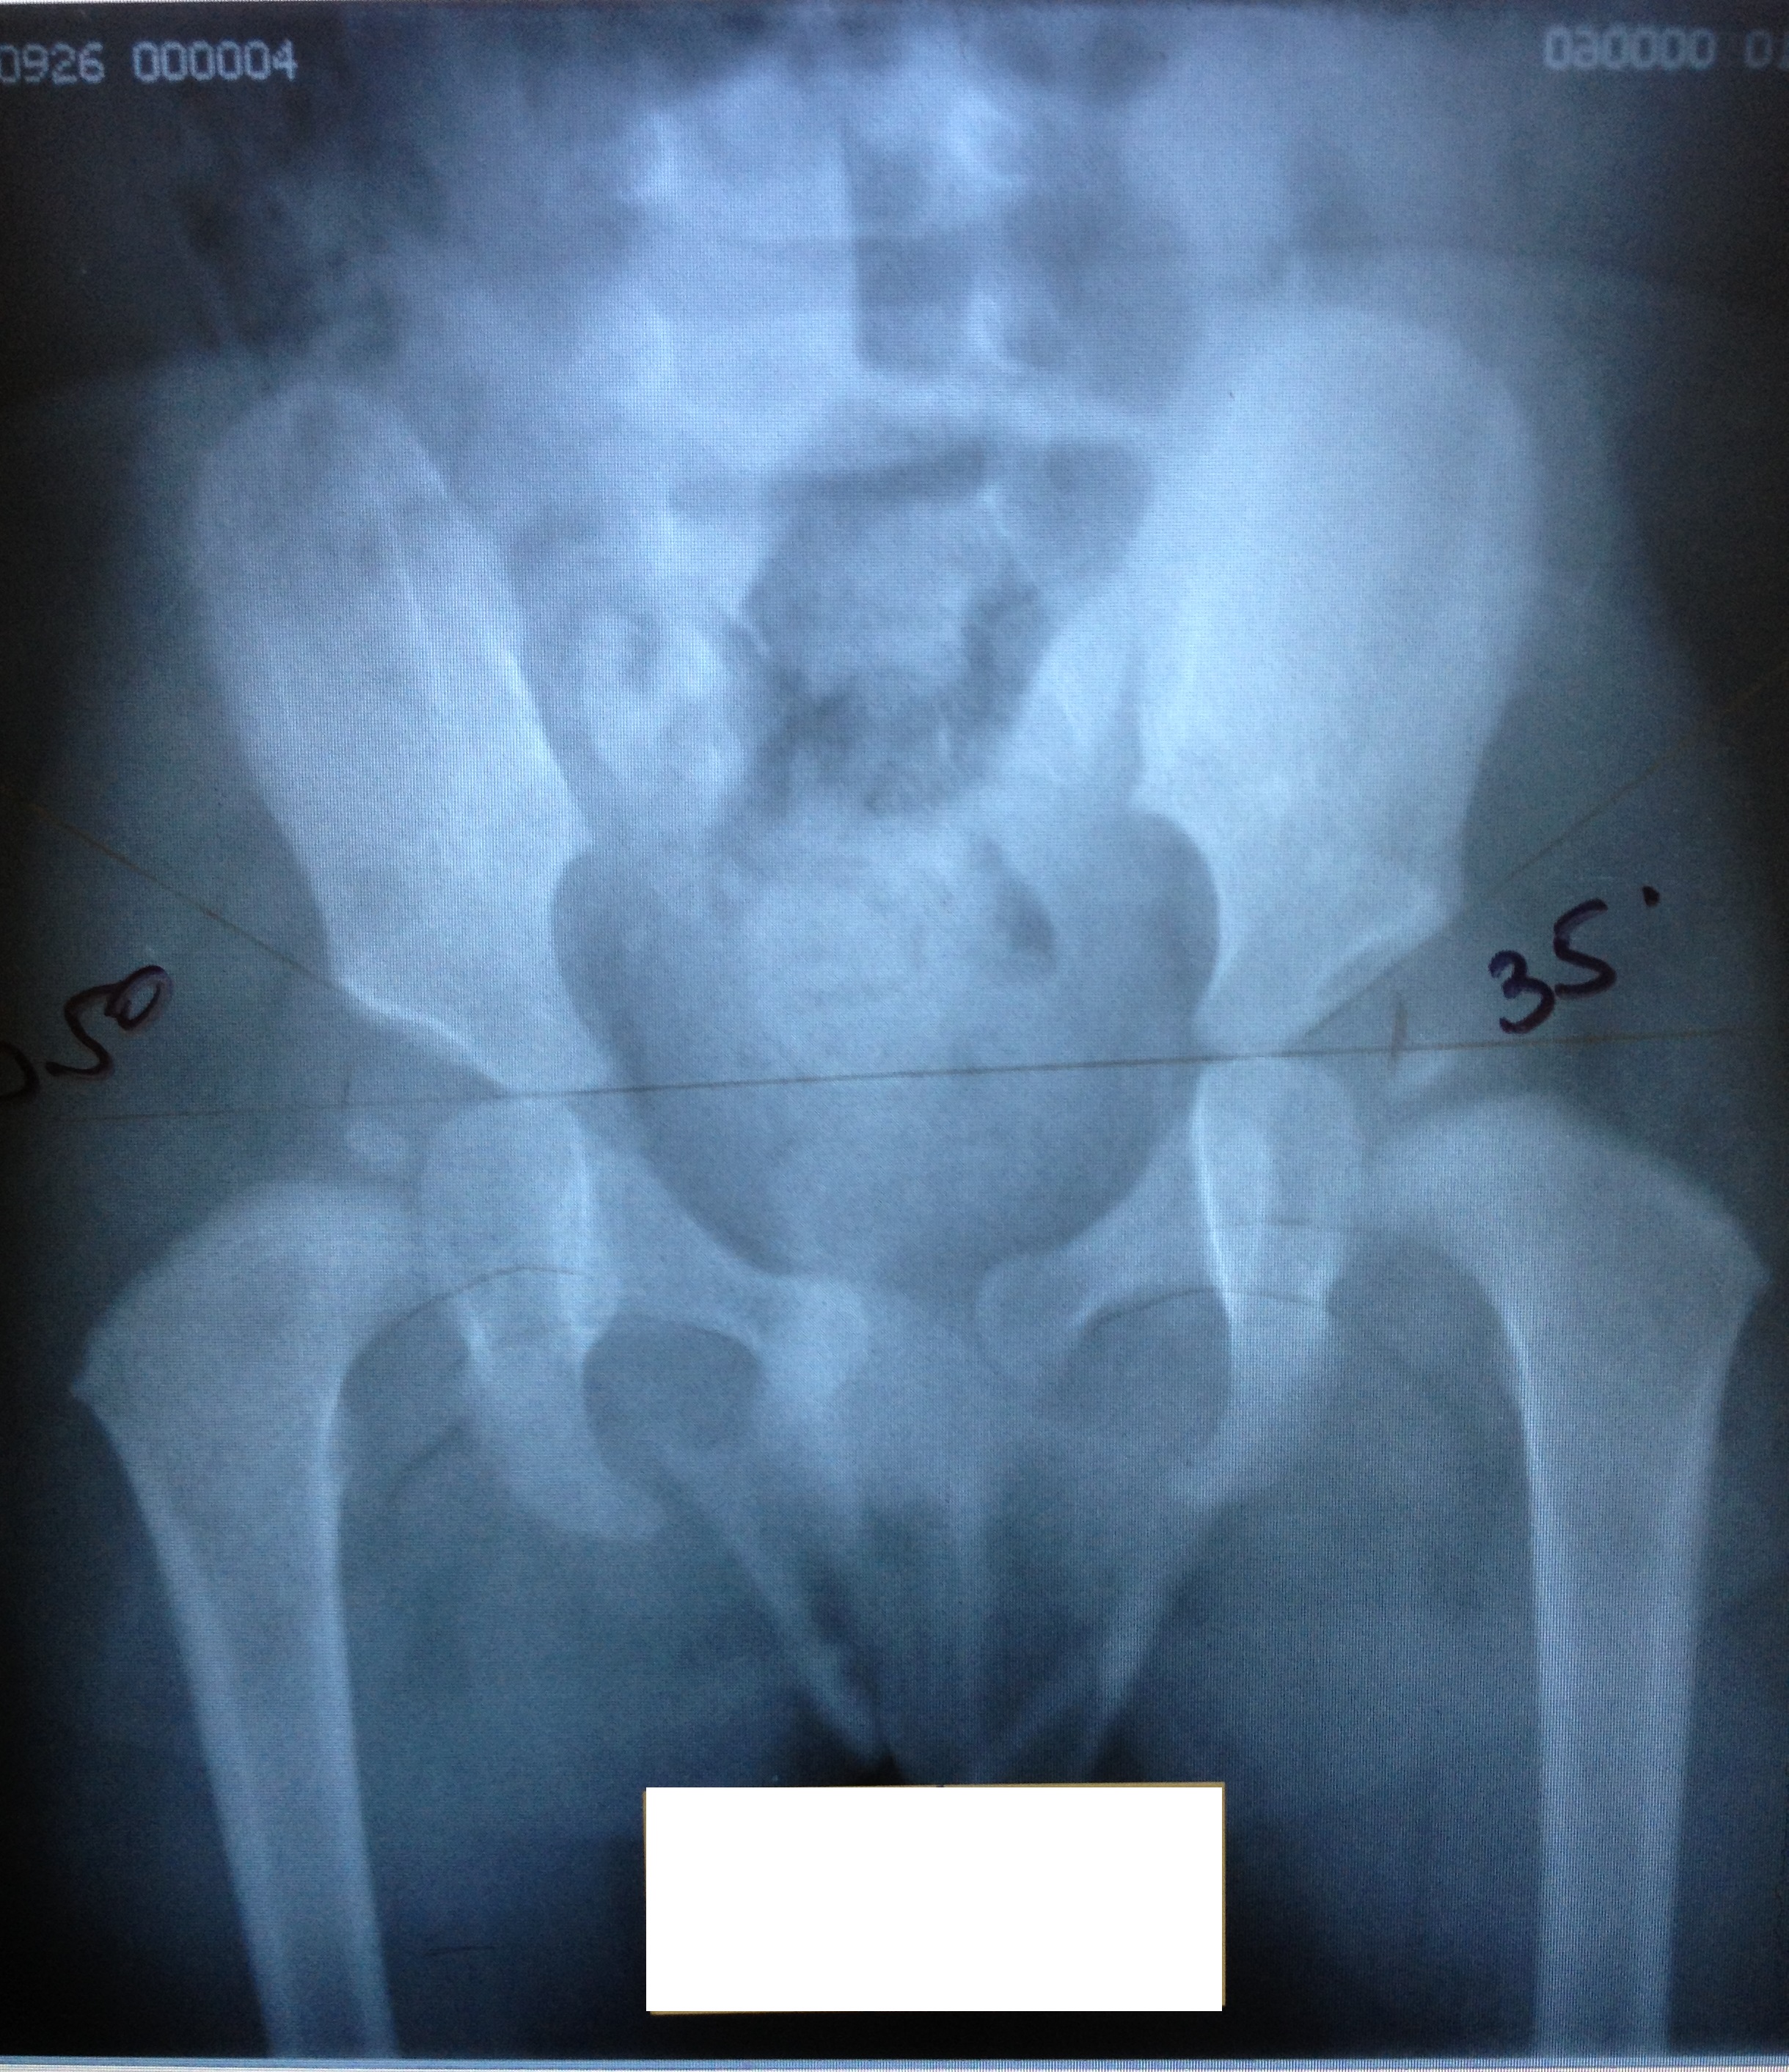

Рентген ТБС: Нормальные показатели

Раздел: Необычные решения